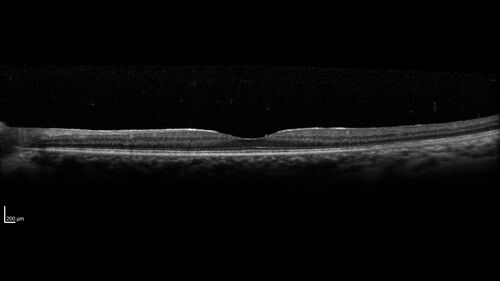

Birdshot Chorioretinitis - Chronic Untreated with Drusen Like Material in Macula

72 year old female with vision changes for years just now diagnosed with Birdshot.